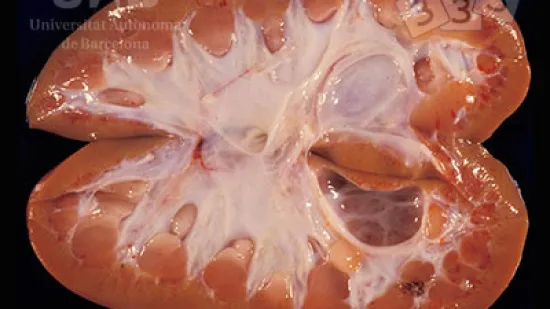

Semaine du 03-Mai-2021

Sur cette photo, on observe une atrophie thymique sévère sur un porcelet; de fait il y a un reliquat dans la zone péricardiaque, autour de la cavité thoracique. Lequel de ces agents infectieux peut avoir provoqué cette lésion ?